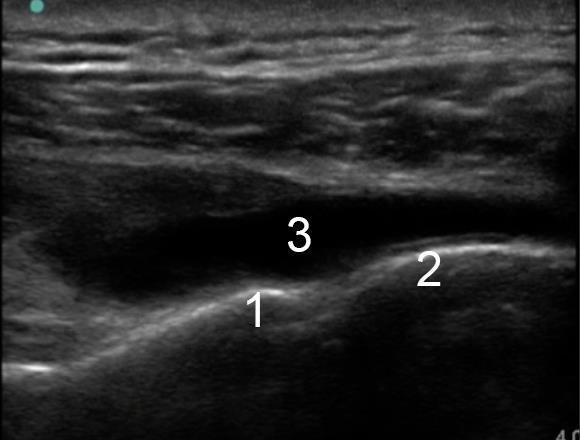

Image : Épaule, Épanchement de l'articulation gléno-humérale

1. Cortex glénoïdien

2. Tête de l'humérus

3. Épanchement